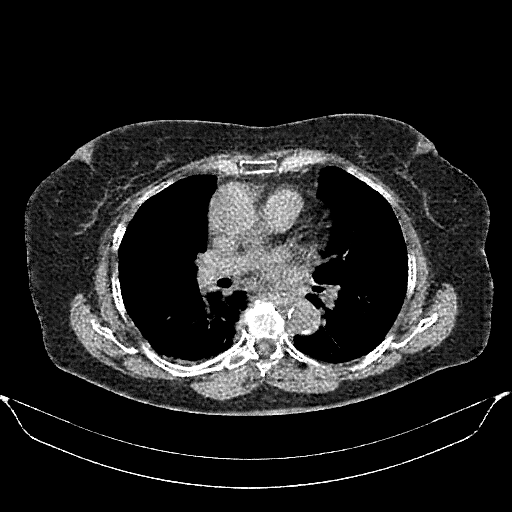

Generated VENOUS CT scan (A→B translation)

Full window (WL 1023.5, WW 4095 β†’ Low βˆ’1024, High +3071)

Lung window (WL -600, WW 1500 β†’ Low βˆ’1350, High +150)

Mediastinum window (WL 40, WW 400 β†’ Low βˆ’160, High +240)